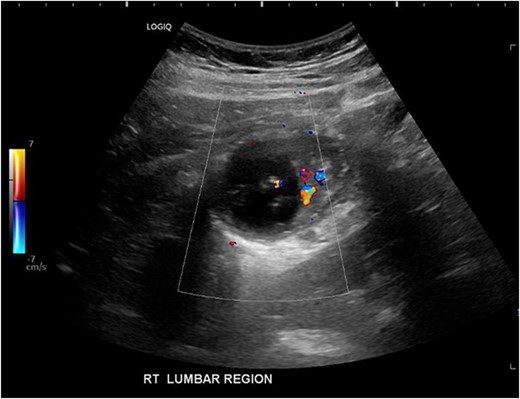

His white cell count was 12.7 × 109/L (reference range 3.7–9.5 × 109/L) and c-reactive protein was 39 mg/L (reference range ≤ 4 mg/L). Hydatid and entamoeba serologies were negative. Carcinoembryonic antigen was elevated to 11.4 ug/L (reference range ≤ 3 ug/L). Abdominal ultrasound showed an uncharacterizable RLQ cystic structure with calcification (Fig. 1). Subsequent computed tomography (CT) scan demonstrated a 56 mm × 43 mm × 58 mm ovoid ascending colon mass with central low density and rim enhancement (Fig. 2). Ileocolic lymphadenopathy up to 7.5 mm in diameter was noted with no evidence of distant metastatic disease.

Ultrasound image demonstrating a cystic lesion with internal calcification and no hypervascularity.